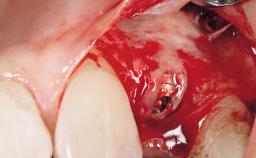

Immediate Flapless Placement of an Implant in a Maxillary Right Lateral Incisor Site

This 43-year-old male patient, a non-smoker, came to our practice because of a fracture of tooth 12 caused by a bicycle accident. Due to the combined para- and infrabony crown and root fracture, tooth extraction, and subsequent implant placement were suggested to the patient as the therapy of choice. The patient had high esthetic expectations with regard to the treatment outcome and asked for an immediate fixed provisional restoration. His individual esthetic risk profile summed up to a medium esthetic risk.

Loading Protocol Immediate

Provisional Implant-Supported Prosthesis Prosthodontic margin > 3 mm apical to mucosal margin Prosthodontic margin > 3 mm apical to mucosal margin